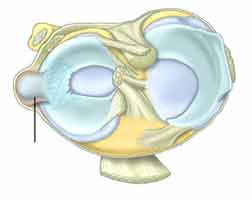

۱- استئونکروز: یکی از شایع ترین عللی که سبب بروز درد زانو هنگام شب می شود، استئونکروز است. استئونکروز به معنای مرگ استخوان می باشد.

در طی این بیماری، استخوان ها جریان خون خود را از دست می دهند و شروع به مردن و از بین رفتن می کنند.

یکی از مهم ترین قسمت های استخوانی بدن که مورد حمله استئونکروز قرار می گیرد، بخش برجسته استخوان ران در قسمت داخلی استخوان زانو می باشد. اما ممکن است این از بین رفتن در قسمت خارجی زانو هم اتفاق بیفتد.